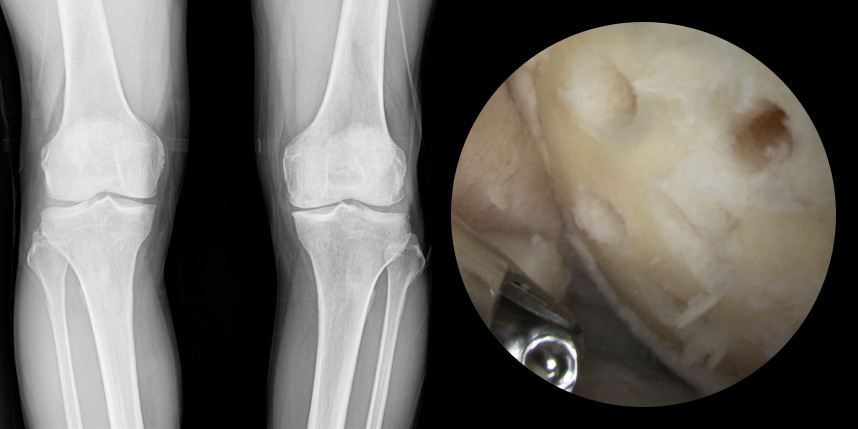

연골재생술 진행

(미세천공술 + alpha)

타병원 미세천공술 실패 후 통증으로 내원하신 사례

* 환자에게 받은 소중한 자료입니다.